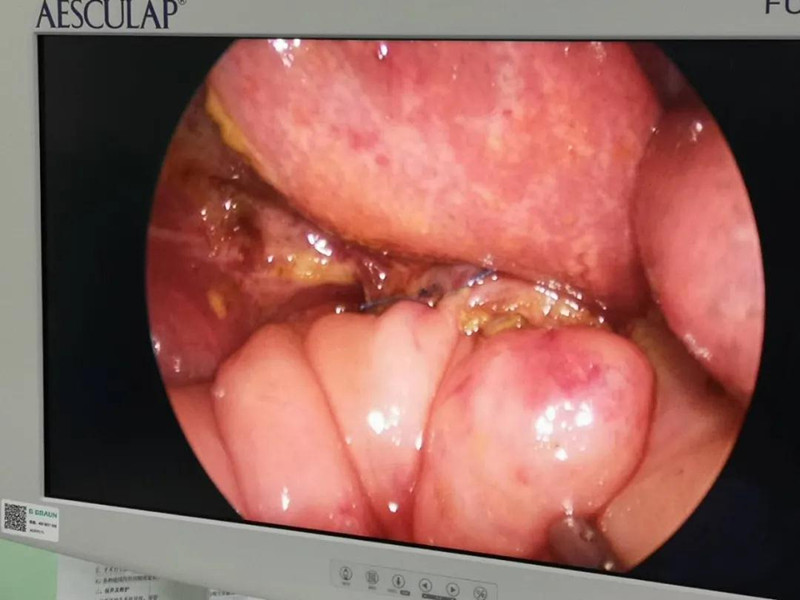

最近半个月,长春市26个月女宝馨馨(化名)脸色不好,全身发黄严重,还伴随发烧。9月23日,馨馨被家人带到德州扑克游戏网 诊治。经检查,馨馨全身发黄是因为患有黄疸,而黄疸的出现是因为胆总管发生病变,“胆总管呈现囊性扩张,下边出口被堵住,胆汁进不到肠腔里,导致孩子出现黄疸、肝功不好、白土便症状。而且胆总管胀大后,还有癌变的风险,”普外、新生儿外科主任崔钊说,馨馨需要尽快手术。为了减少损伤,崔钊主任团队制定的方案是单孔腹腔镜下胆总管囊肿根治手术。

术前准备完毕。 9月25日,馨馨进入手术室。由崔钊主任带队,按照术前设计的方案,经过8个小时的奋战,手术成功了。馨馨肝总管以下病变的胆总管及胆囊全部切除,肝总管断面与肠管吻合接上,让胆汁直接流到肠腔里,帮助消化。如术后不出现胆瘘、肠瘘,没有梗阻,馨馨以后就可以正常生活了。目前馨馨恢复得很好,黄疸渐渐缓解,肝功正常,白细胞也降下来了,排气、排便都没问题,引尿管里也没有异常东西。

最难:防止门静脉出血

崔钊主任说,术前大家最担心的是门静脉出血,因为它比动脉出血更凶险,可危及生命。“馨馨来院时已经出现炎症,周围粘连严重。而静脉左侧临着肝总动脉,下边连着十二指肠乳头、胰腺,它和背侧的门静脉紧贴着,一不小心,就会导致门静脉出血。”

为了规避出血风险,术前,团队备足了血,又配备一名助手,一旦术中门静脉出血,马上开腹止血。另外,还有肝脏动脉变异的可能,幸好,术中这些个担心都没有出现。